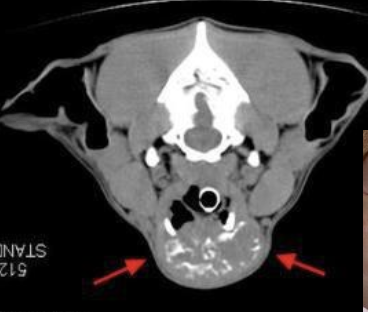

what is the location of thyroid tumors in dogs?

~60% of cases have bilateral disease

can also have ectopic thyroid neoplasia (can occur anywhere from base of tongue to base of the heart)